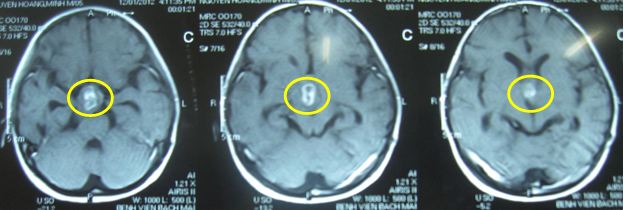

Sau xạ trị gia tốc đợt 2: Hình ảnh chụp cộng hưởng từ (MRI) sọ não:

Kích thước u thu nhỏ lại rõ rệt (trong vòng màu vàng)

Trước điều trị: Đau đầu, U kích thước lớn: 4x5cm

Sau xạ trị: Lâm sàng tốt lên nhiều, u bé lại rõ rệt: 1,5x1,8cm

Hình ảnh MRI sọ não. Trước điều trị (hình bên trái): khối u sọ hầu (vòng tròn xanh). Sau điều trị 18 tháng (hình bên phải): khối u tan hết.